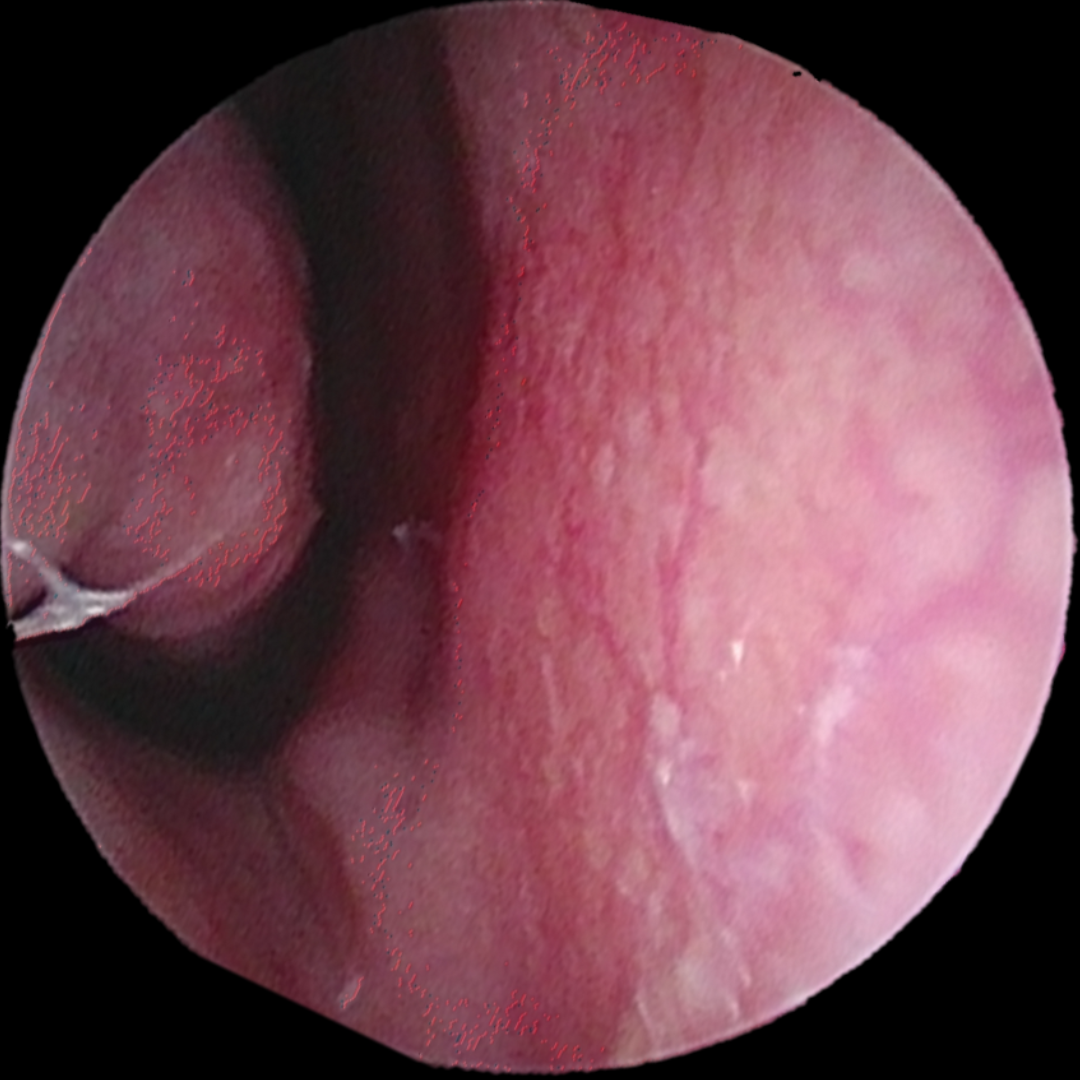

Figure 1: Dilated blood vessels on the nasal septum in Kesselbach’s plexus

Nosebleeds are common in children and seldom a reason for serious concern. The most common cause of nosebleeds in children is dryness in the nose, often in combination with rubbing the nose, blowing the nose, or picking the nose. Almost all nosebleeds in children come from the anterior nasal septum in a region known as Kesselbach’s plexus. This is an area where several different feeder vessels come together, are often sizable, and are poorly protected by the overlying skin that can dry out, crack, and then produce significant bleeding.